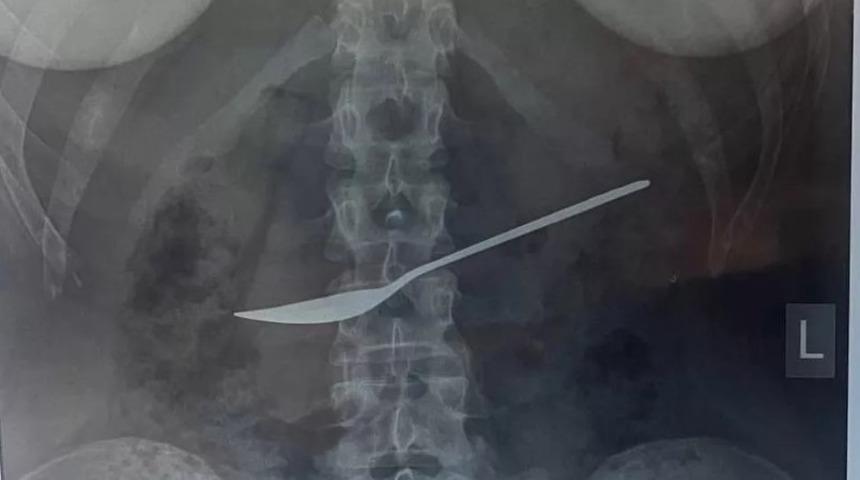

MYNET|DIŞ HABERLER Rusya'nın Vologda eyaletindeki bir hastaneye giden ismi açıklanmayan kadın şiddetli karın ağrısından şikayetçiydi. Hastaneye giden genç kadının ağrısının nedeninin bulunması için bir dizi röntgen çekildi. Röntgen sonuçlarında ismi açıklanmayan kadın hastanın midesinden 20 cm'lik metal bir kaşık çıkartıldı.

Hastanın acilen ameliyata alındığını belirten Doktor Dmitry Vankov, "Hastaya hemen özofagogastroduodenoskopi uygulandı. Midenin video endoskop kullanılarak incelenmesi tanıyı doğrulama konusunda bize yardımcı oldu. Kaşık özel bir halka ile yakalandı ve yemek borusu yoluyla mideden çıkarıldı." ifadelerini kullandı.